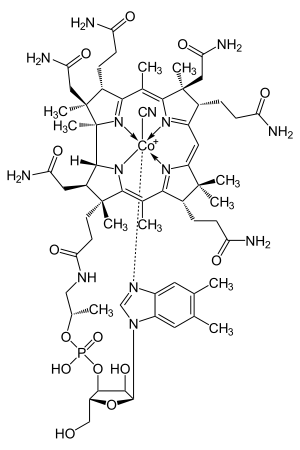

| Cyanocobalamin | |